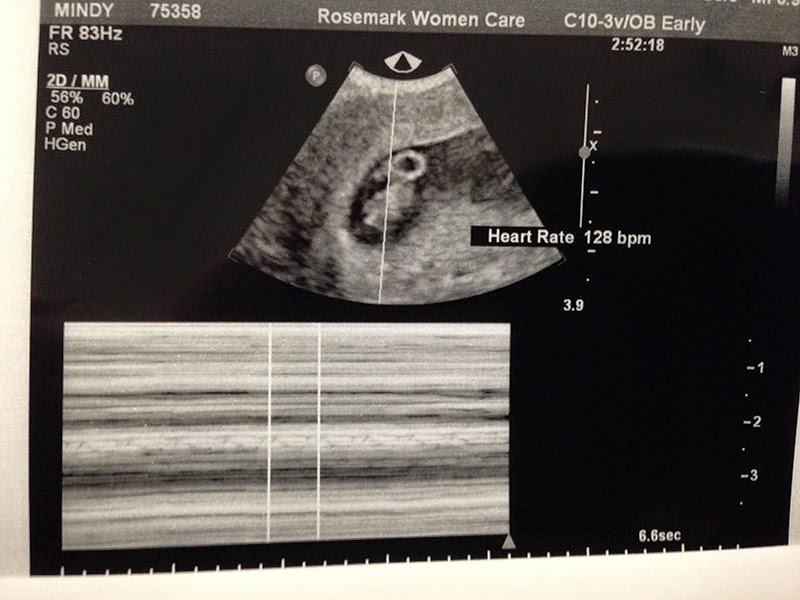

Then, I had to wait until I was 8 weeks along to have my first OBGYN visit and ultrasound! It was torture and since we weren't telling Facebook or any social media it was super difficult to keep our excitement to ourselves.

Finally the day arrived! And we got to see our little squid-looking baby for the first time! Made everything more real to me!! And everything was measuring and looking great! We even heard the heartbeat!